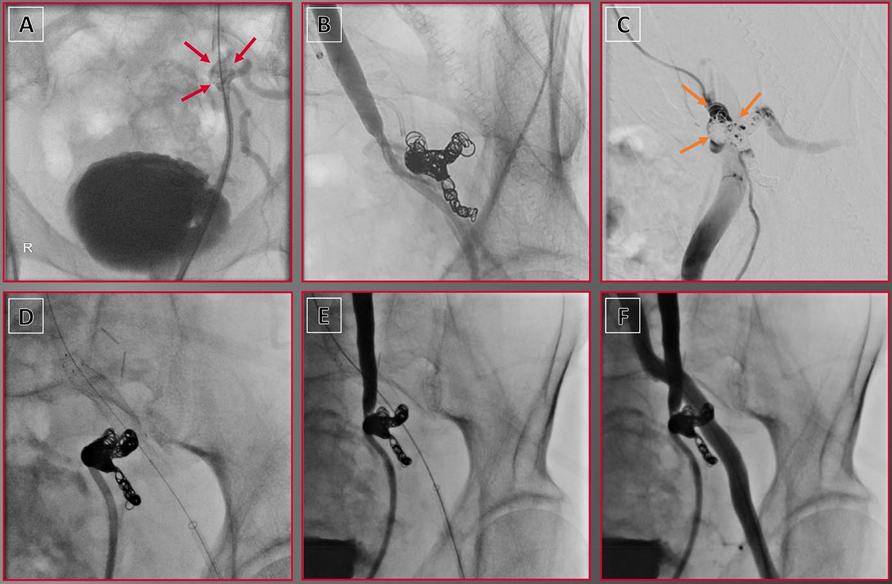

原文图1. 使用外部器械进行病变修饰。(A)压裂技术:利用液压裂解深层钙化斑块。(B)DECIAP技术:使用动脉钳夹碎钙化斑块。DECIAP:钳夹诱导动脉斑块开裂直接内膜切除术。

压裂治疗前后及球囊血管成形术后病变形态与IVUS评估的MLA代表性病例。A 初始血管造影显示右侧股总动脉存在重度钙化斑块。B 初始IVUS评估示术前最小管腔面积(MLA)为2.1 mm²(管腔直径:1.7 × 1.3 mm)。C、D 使用7.0 mm非顺应性球囊行球囊血管成形术后,后续血管造影及IVUS显示残余狭窄33%,术中MLA为5.8 mm²(管腔直径:3.0 × 1.7 mm)。E 压裂治疗后,最终血管造影显示满意影像,狭窄率17%。F 压裂后IVUS评估显示术后MLA为20.5 mm²(管腔直径:6.1 × 4.3 mm)。缩略语:IVUS,血管内超声;LD,管腔直径;MLA,最小管腔面积。